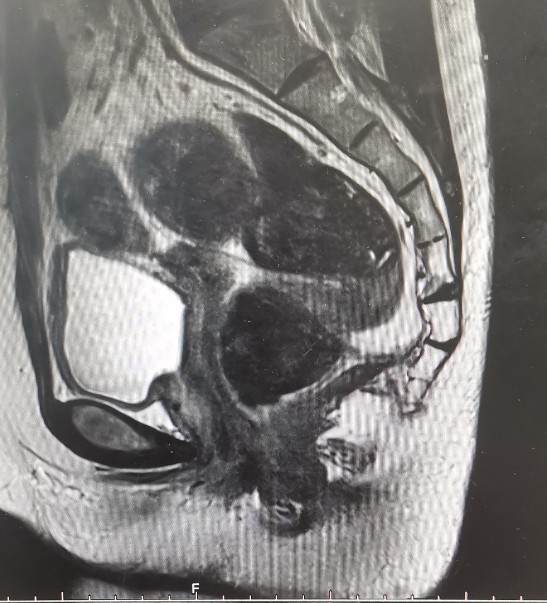

•全腹核磁:子宫术后改变,脂肪肝,双肾囊肿,盆腔少量积液。

轴位T1

轴位T2

矢状位T1

矢状位T2